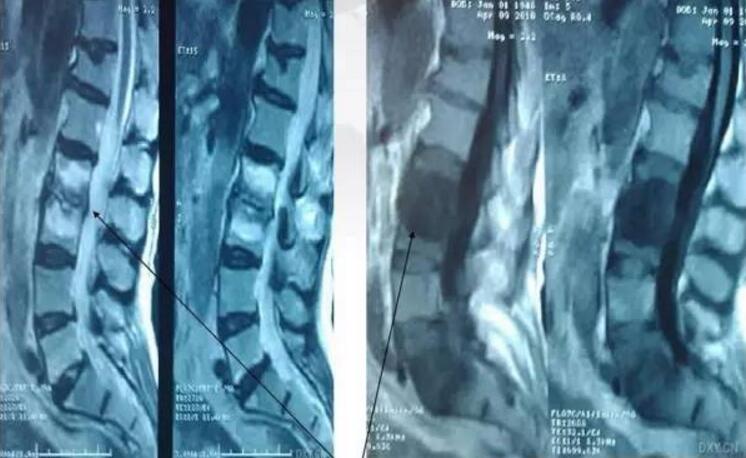

腰椎ct平扫可见其l5s1节段为严重的终板炎